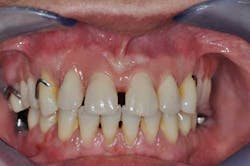

Figs. 8a, b, c, and d: Final results